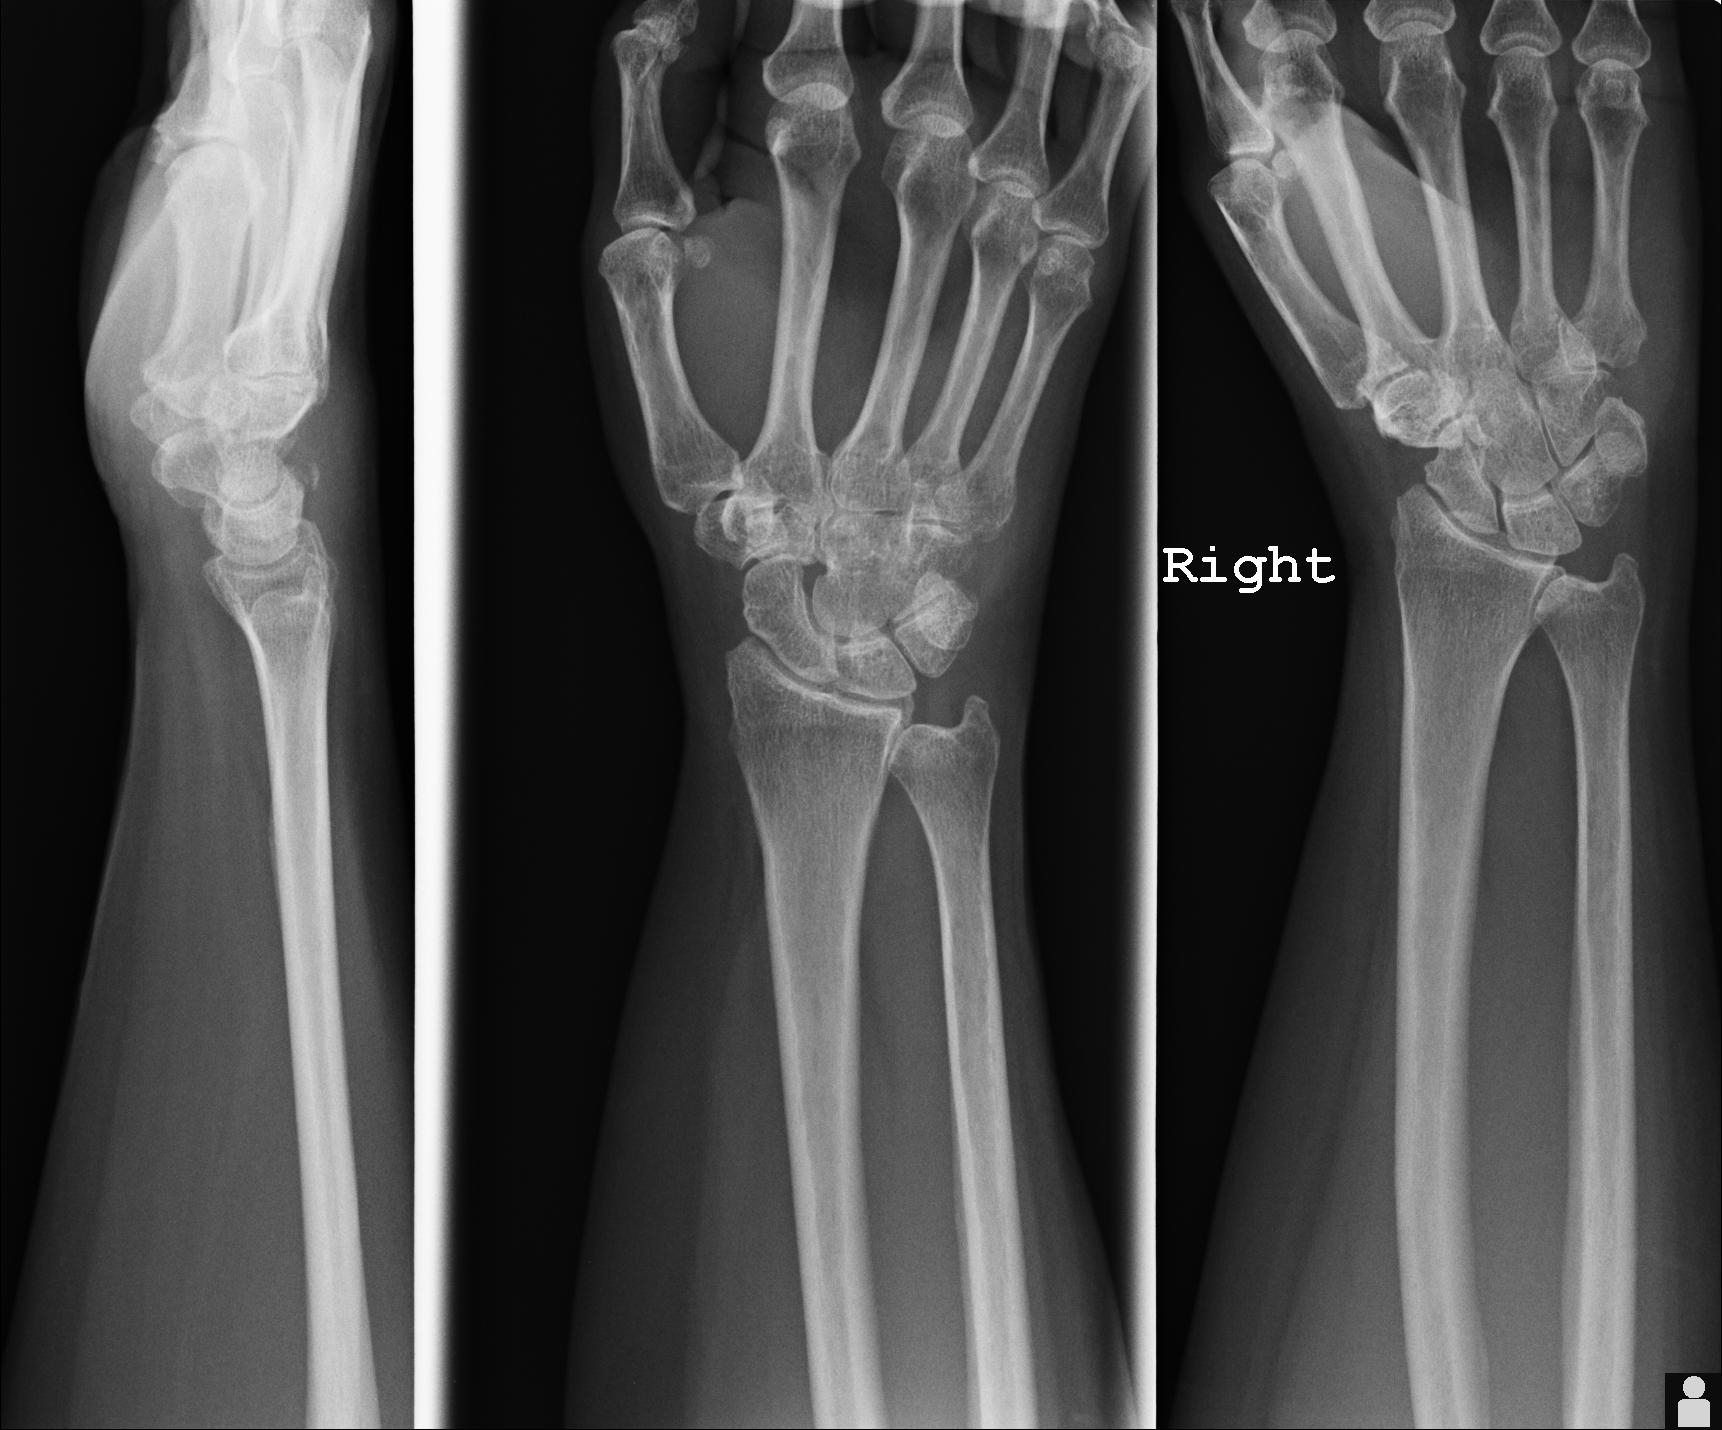

Fractured right-hand wrist. Sprained left hand. One hard cast and one brace. Much awkwardness and difficulty with everyday tasks. Pain. Another exercise in patience and acceptance.